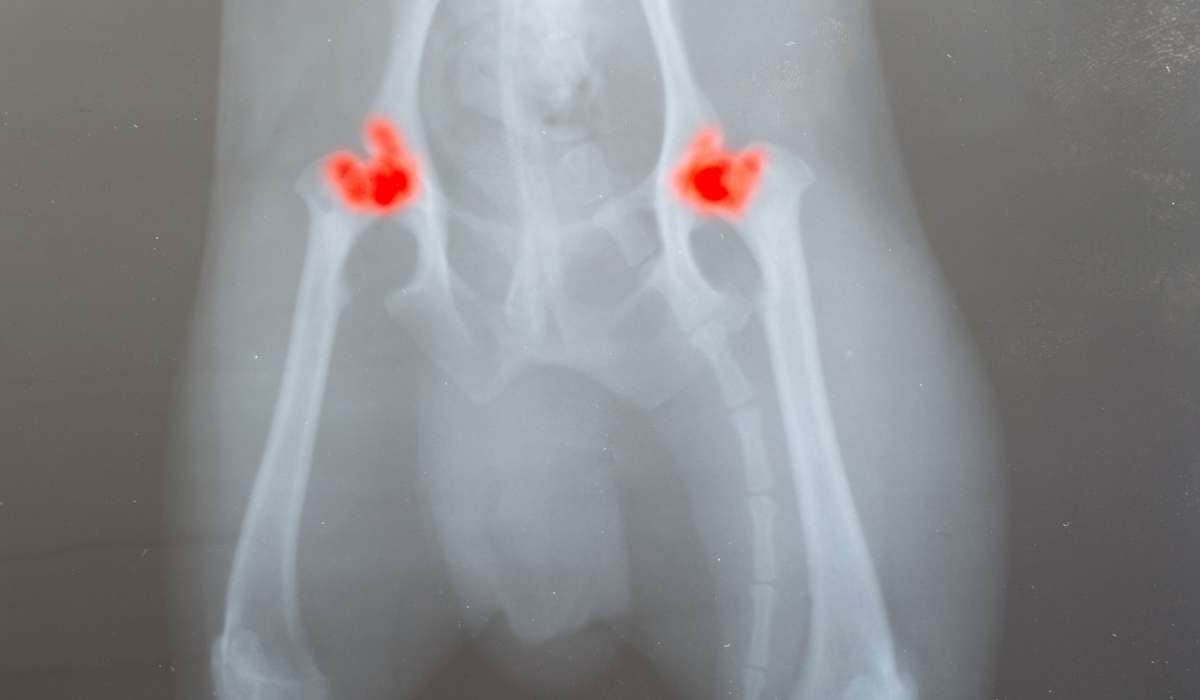

A continuación, programará una cita con su perro para realizar una radiografía a sus articulaciones, para así buscar anomalías tales como cavidades incompletas en la cadera. De no poder observar con claridad el problema, te pedirán realizar un TAC al perro para poder ver en detalle el grado de la enfermedad.

Un veterinario toma una radiografía de las caderas de un perro adulto y asigna un valor a la articulación de cada lado.